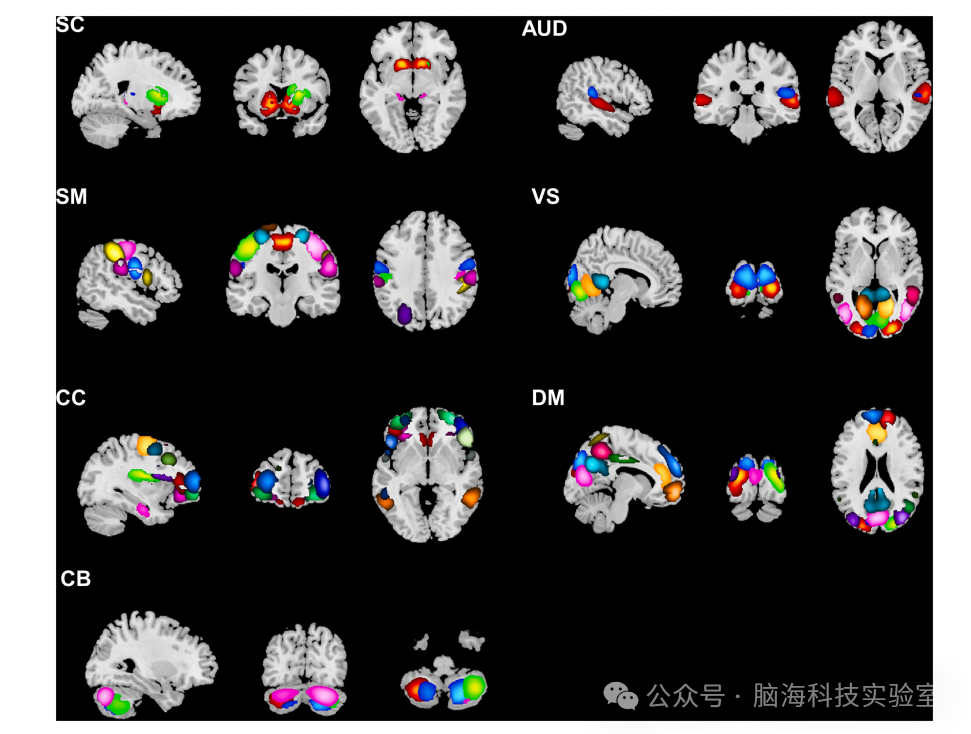

图1 在空间 GICA 中确定了 7 个内在连接网络

研究纳入了159名KOA患者和73名年龄、性别匹配的健康对照者(HS),所有参与者均接受了静息态功能磁共振成像(rs-fMRI)扫描和临床评估。研究者采用基于组独立成分分析(GICA)的方法,识别出七个静息态网络,并分析了这些网络之间的静态和动态功能连接。